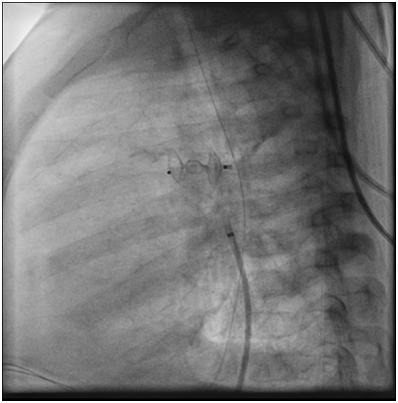

Angiography at the beginning of the cath showed that the PDA had completely disappeared (Figure 3).

Figure 3 Angiogram in the Aorta showed that the PDA disappeared.